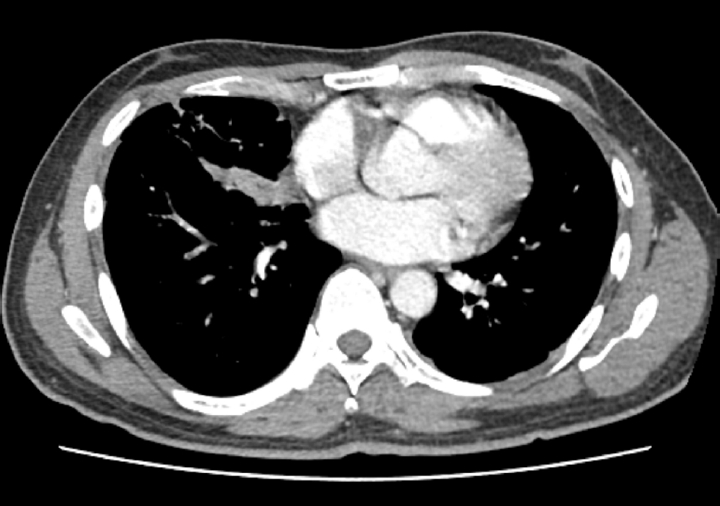

Upon admission, his vital signs were as follows: blood pressure, 100/60 mmHg; pulse rate, 120 beats/min; respiratory rate, 20 breaths/min; and body temperature, 38.2°C. Pulse oximetry revealed that oxygen saturation was 95% on room air. Chest auscultation revealed crackling rales in the lower bibasilar lobes. Initial laboratory investigations showed significant leukocytosis with white blood cell (WBC) count of 28,100 cells/µL and elevated C-reactive protein (CRP) level of 35.39 mg/dL. To evaluate for potential secondary infection, multiple microbiological cultures were performed during the early hospital course. These included blood and sputum cultures on the day of hospital admission (day 1), a follow-up sputum culture on day 2, and sputum and urine cultures on day 3. All cultures yielded no specific growth. Chest radiography revealed bilateral pleural effusions and patchy consolidations in both lower lung fields suggestive of pneumonia (Fig. 1). Contrast-enhanced computed tomography (CT) of the chest revealed ground-glass opacities in the right middle lobe, base of the right lower lobe, and left lower lobe, accompanied by intrinsic air and bronchovascular bundles. Based on these findings, the patient was admitted to the intensive care unit with a diagnosis of encapsulated necrotizing pneumonia.

Fig. 1.

Initial chest radiograph showing bilateral patchy consolidations over lower lung fields with pleural effusion.

Fig. 1. Initial chest radiograph showing bilateral patchy consolidations over lower lung fields with pleural effusion.